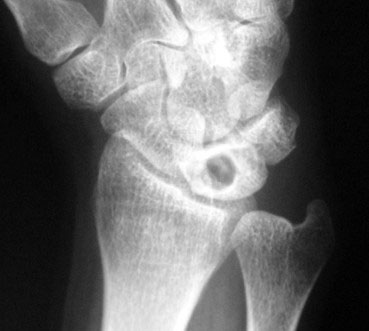

Alteraciones mecánicas o anatómicas, como una discrepancia en la longitud de los huesos: tener un cúbito corto (figuras 1 y 2) y una determinada forma anatómica de semilunar (tipo I) (figura 3).

Figuras 1 y 2: cúbito minus o corto (predisponente de Kienböck)